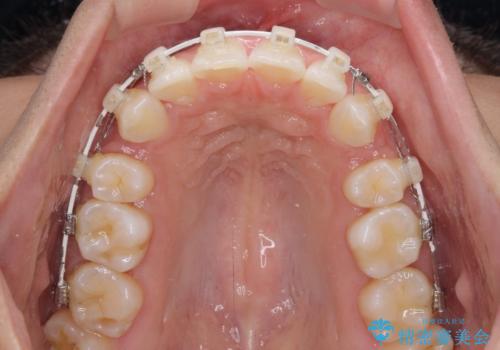

- 審美装置

- 2年3ヶ月

- 10-30回

- 下唇が突き出るような口元の突出感が気になるとのことで来院された患者様です。

上下顎ともに前突した歯列であったので、上下ともに左右の第1小臼歯4本を抜歯し、ワイヤー装置にて矯正治療を行うこととしました。